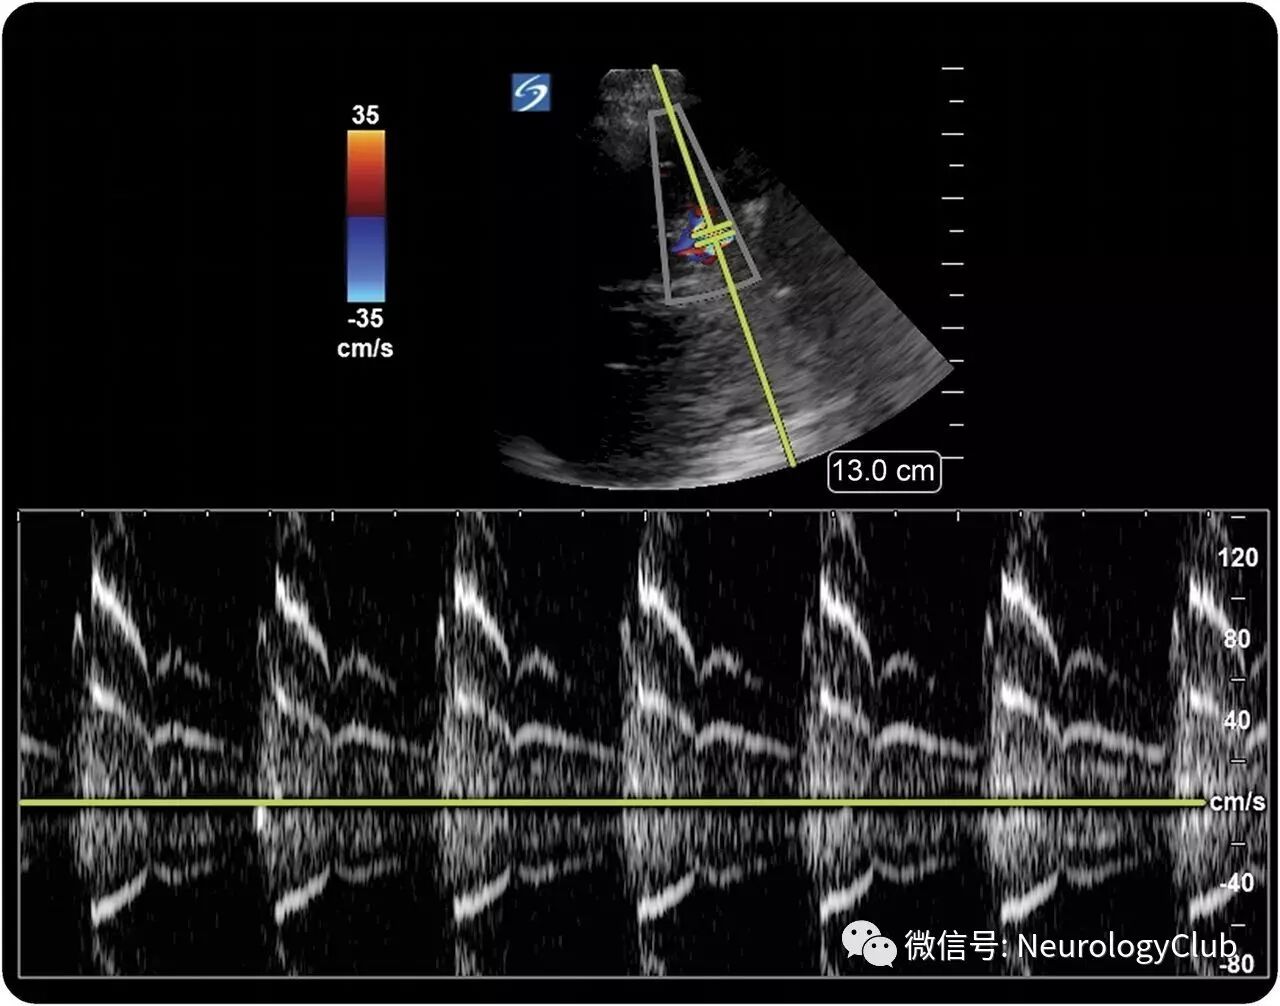

当抱着5岁女儿时,母亲注意到其右侧颅内脉动性音乐性杂音。这一既往体健的女孩接受了各项检查,证实右侧颈内动脉末端存在严重的狭窄,经颅超声提示对侧颈内动脉颅内段亦有狭窄。尽管目前没有典型的侧支循环,但仍高度怀疑moyamoya综合征(图1和2)。音乐性杂音是严重狭窄动脉中高速血流的征象,在经颅彩色超声上可检测到,即所谓的“海鸥哭声”——通过镜像平行线(mirror-image parallel strings)能可听化并可视化呈现(图1,视频)。

(图1:镜像平行线上可见颈内动脉末端潜在的严重狭窄)

(视频:经颅彩色超声:镜像平行线和大声的音乐性杂音让人联想到海鸥哭声,为严重血管疾病的征象